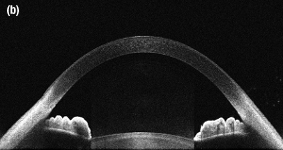

An Image of the Anterior of the Eye Taken with the SLD830S-A10 in a Modified Ganymede System

SLD830S-A10

830 nm SLD, Gain Ripple: ≤0.15 dB

OCT用途例

それぞれの画像の組織内深度は6.2 mmで、36 kHzのA-スキャンレートで撮影されています。